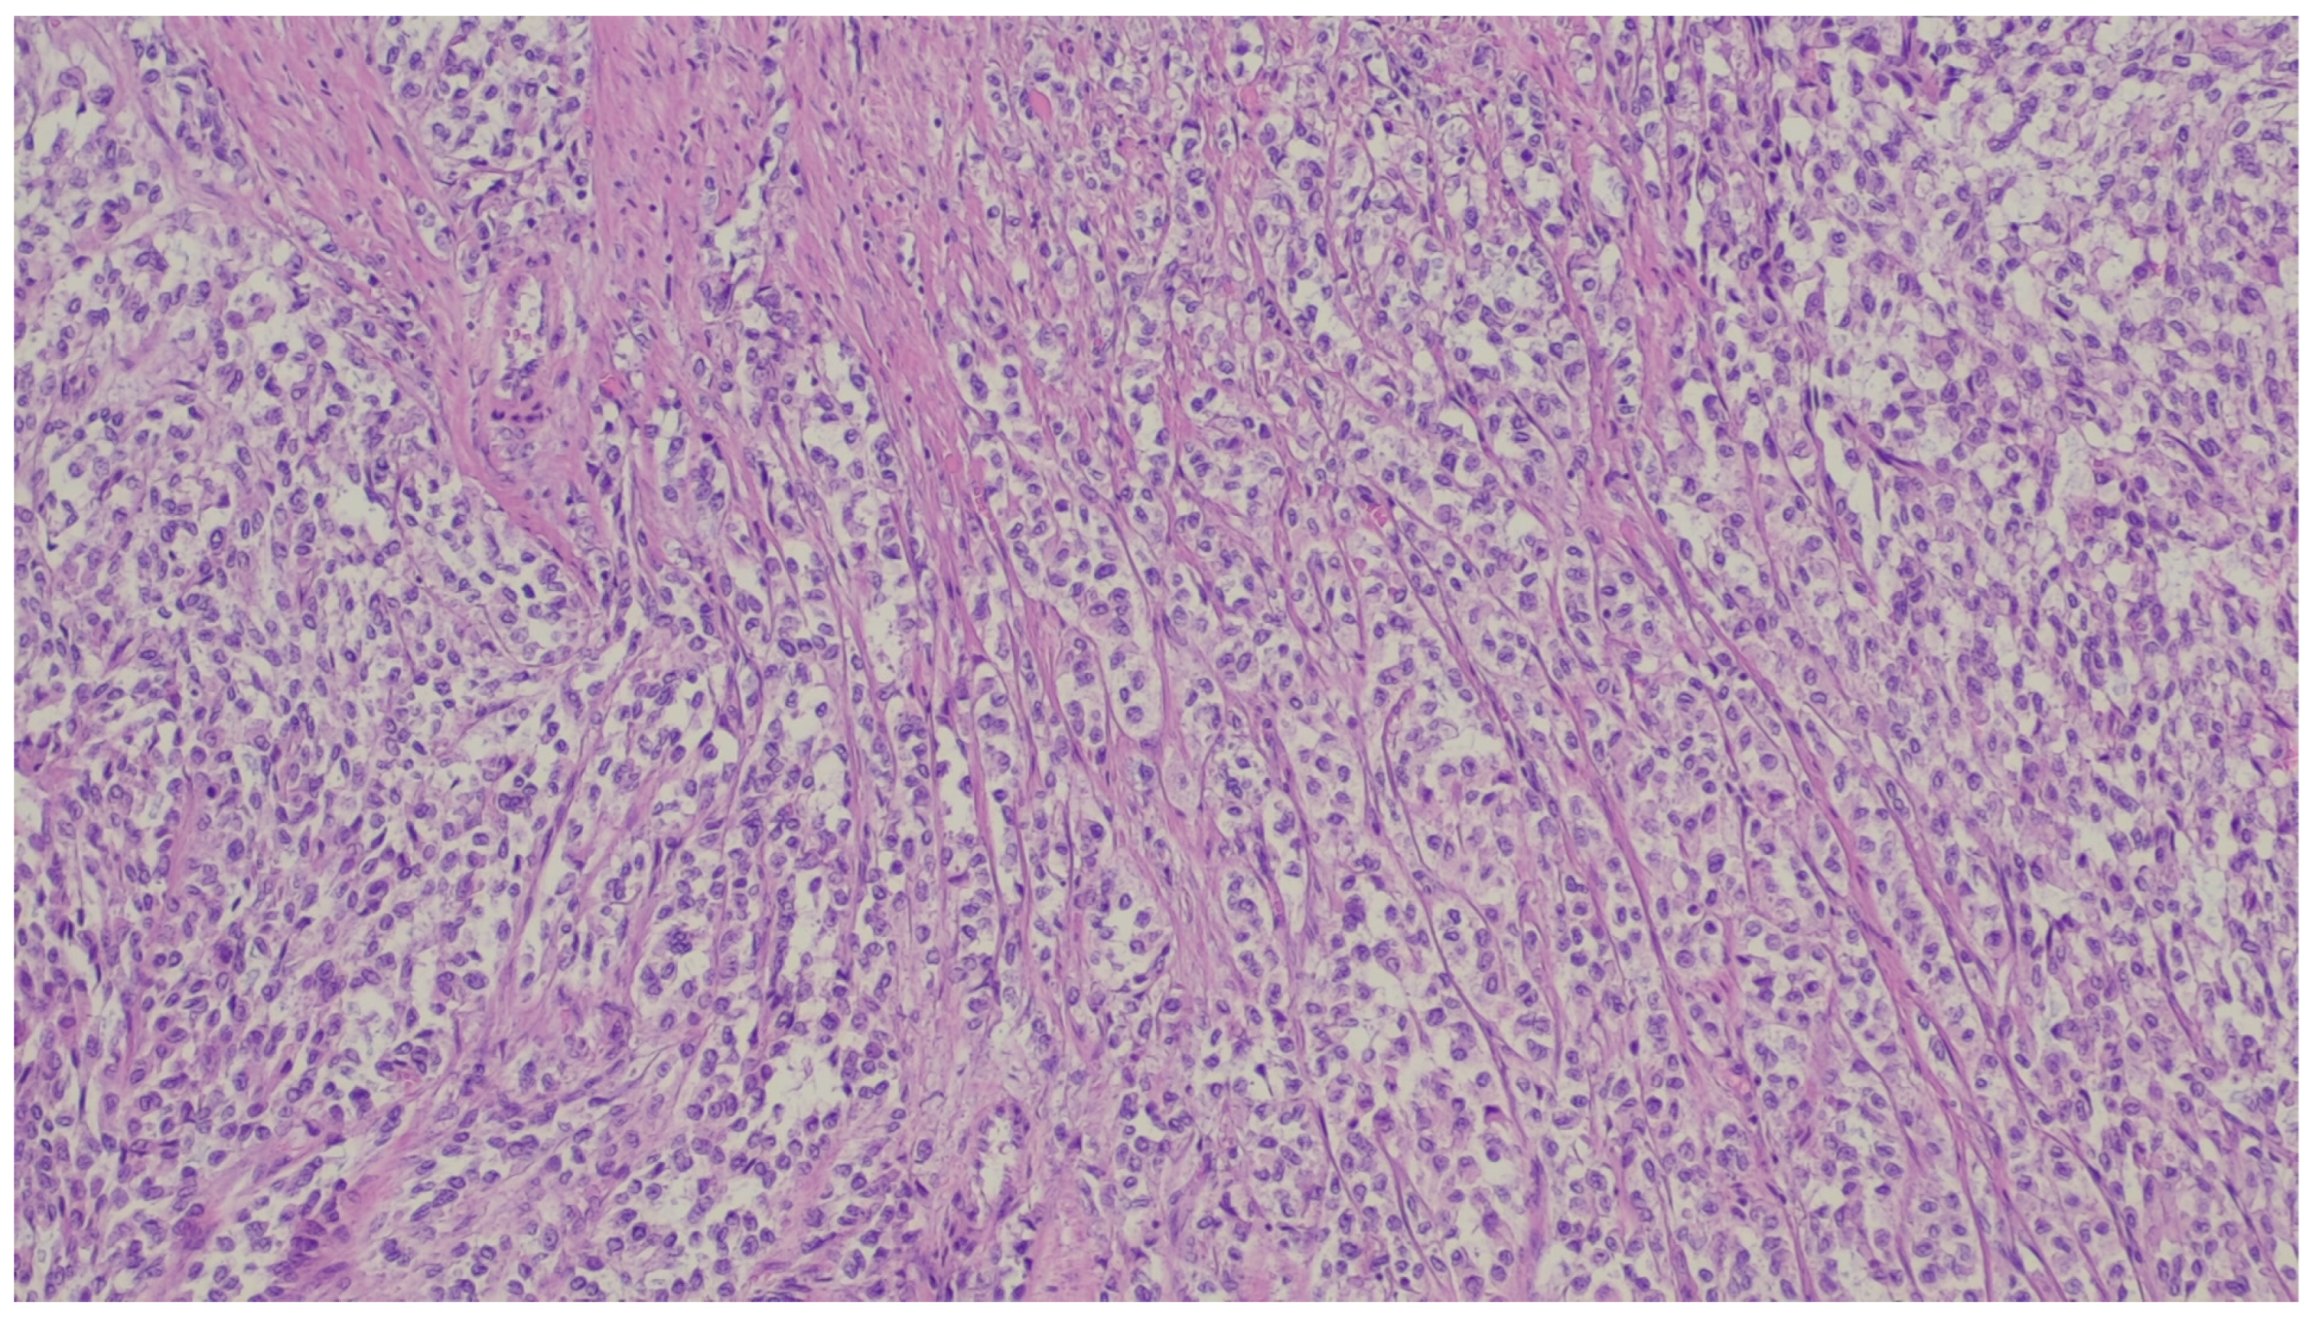

| Fibromatosis | 30 and 40 years | Mesentery of the small bowel | Abdominal pain | Long fascicles of spindle cells with ovoid nuclei without atypia or necrosis | Β-catenin |

| Leiomyosarcoma | Very rare in the GI tract | Small intestine | Abdominal pain, obstruction | Of fascicles of spindle cells with atypia, centrally placed cigar-shaped nuclei, and eosinophilic fibrillary cytoplasm with high mitotic counts | α-sma, desmin, caldesmon |